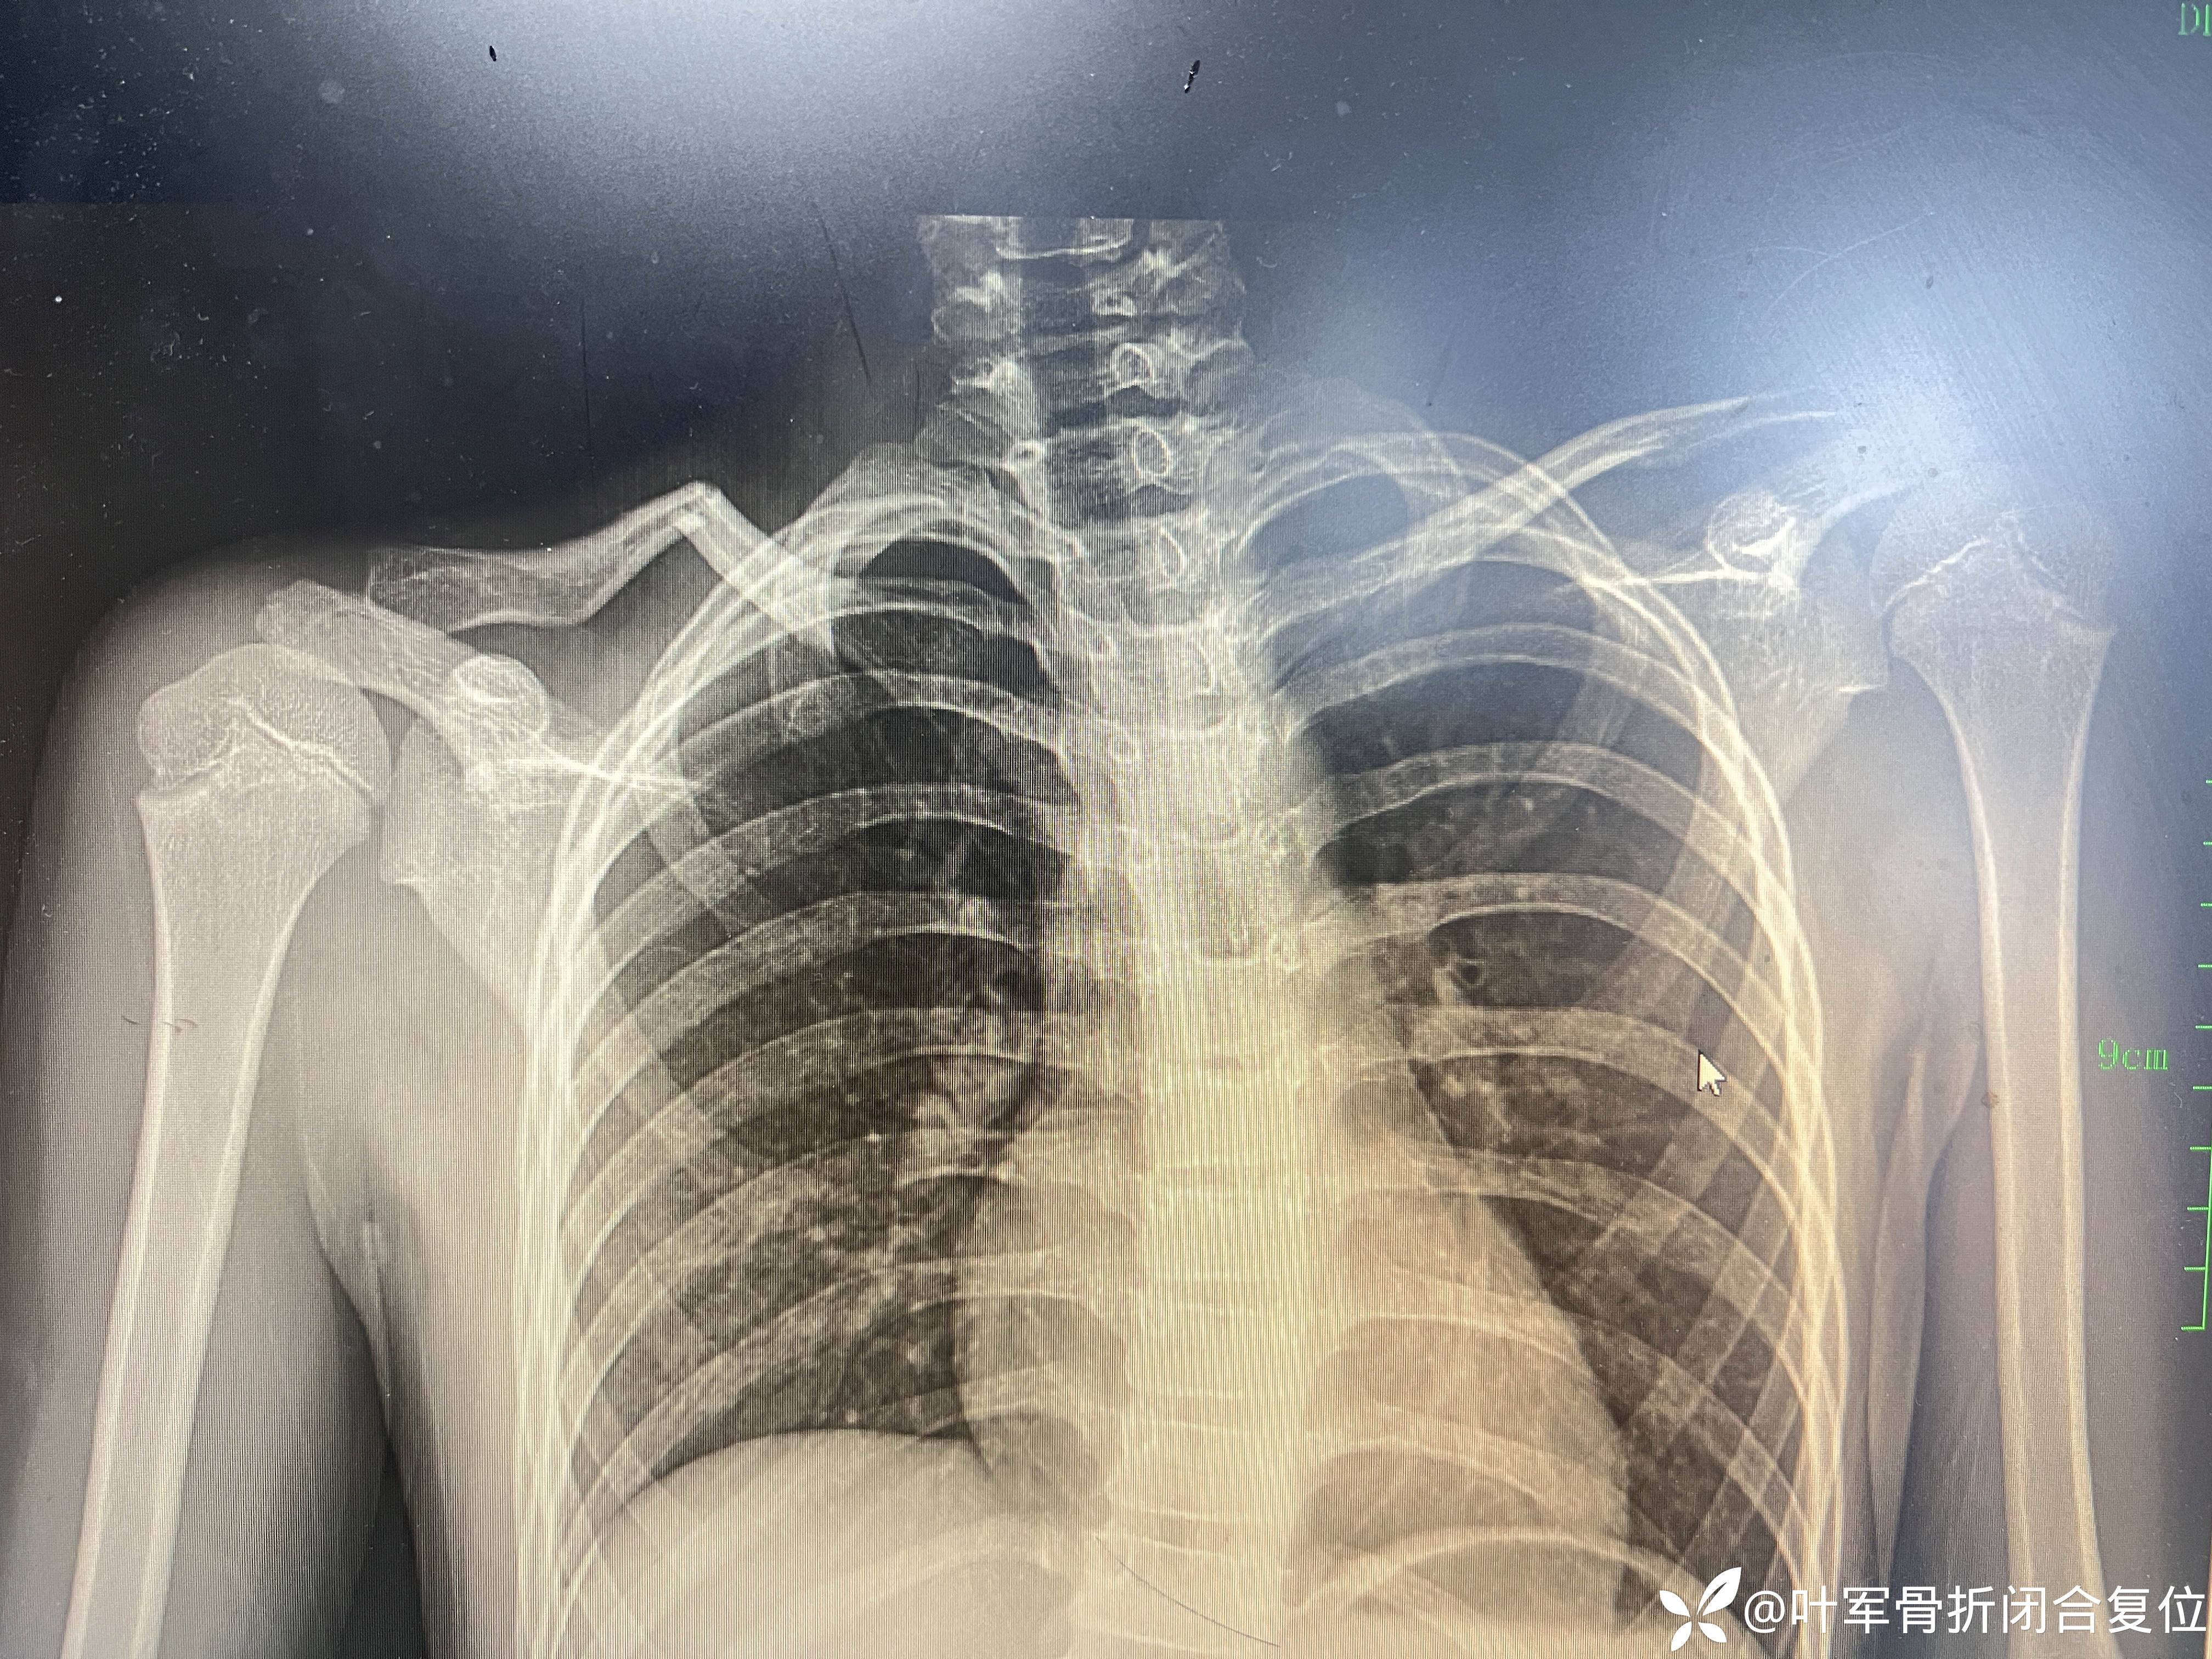

简单锁骨骨折闭合复位

11岁儿童锁骨骨折 成角畸形